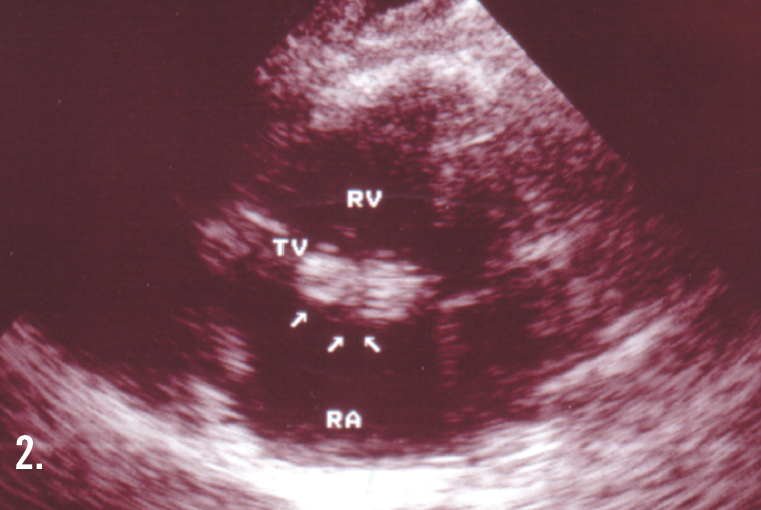

In a 2-dimensional echocardiogram of the right atrium and right ventricle (Figure 2), 3 arrows point to the vegetation. (RV, right ventricle; LV, left ventricle; RA, right atrium; LA, left atrium; TV, tricuspid valve.) The results of 3 sets of blood cultures were positive for Staphylococcus aureus, and the patient was given intravenous vancomycin for 6 weeks. This therapy failed, and he then underwent tricuspid valve replacement.